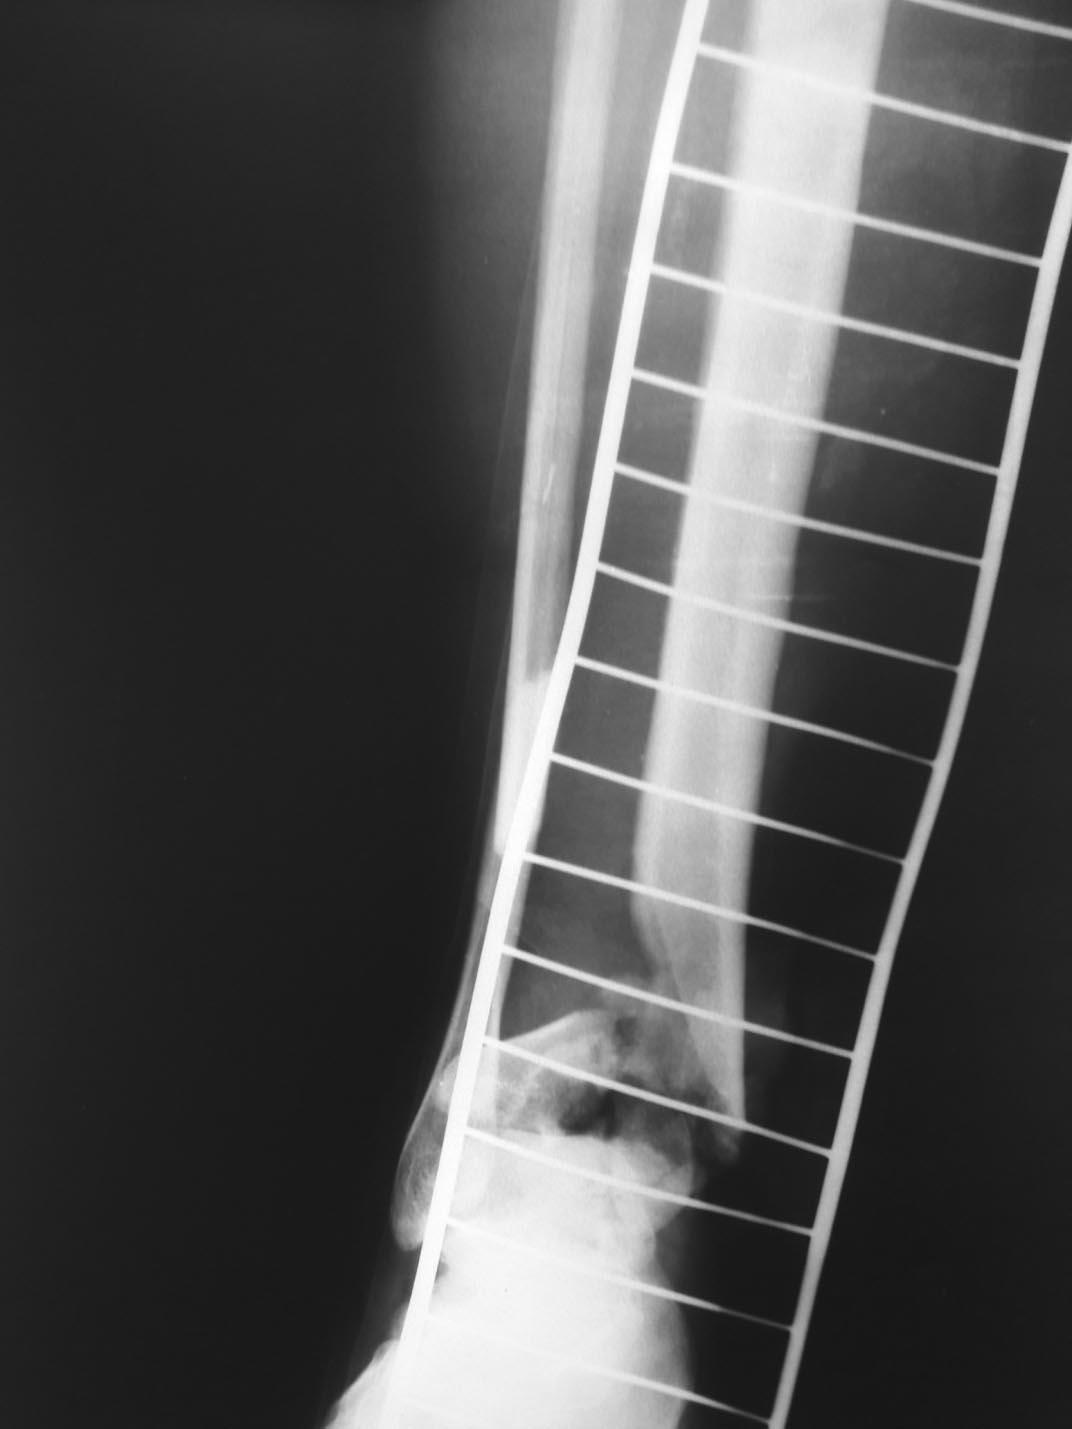

[Ortho] Открытый перелом голени

фото раны и рентгеновские снимки